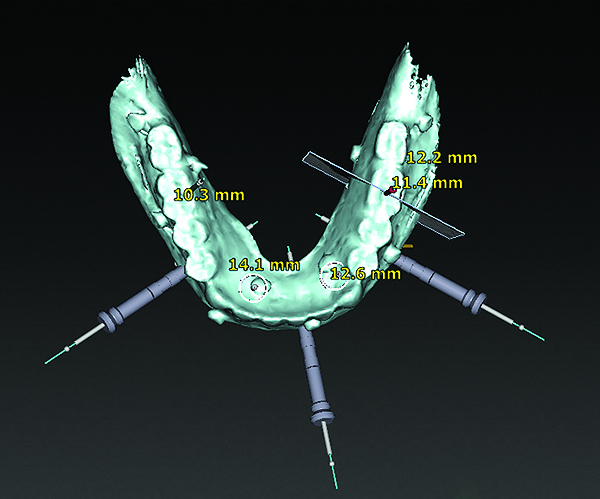

3D radiographic scans obtained using the single scan protocol can be combined with digital mock-ups performed on intraoral optical scans or scans of casts,20 using the existing natural teeth as fiduciary markers. Different masks for bone, teeth, gingiva, and implants can be designated and processed (Figure 13 and Figure 14). This technology allows for greater accuracy, since implant position will be determined based on natural teeth (fiduciary markers) that are likely to be more stable and accurate than fiduciary markers placed on a radiographic guide.

(13) An optical scan of patient’s teeth and diagnostic wax-up was combined with CBCT to facilitate treatment planning of implant placement. Note that there is a need for sinus augmentation to accommodate a dental implant on the right image (blue: tooth contours determined from wax-up/optical impression, red: soft tissue outline).

Figure 13

(14) An optical scan of patient’s teeth and diagnostic wax-up was combined with CBCT to facilitate treatment planning of implant placement. Note that there is a need for sinus augmentation to accommodate a dental implant on the right image (blue: tooth contours determined from wax-up/optical impression, red: soft tissue outline).

Figure 14